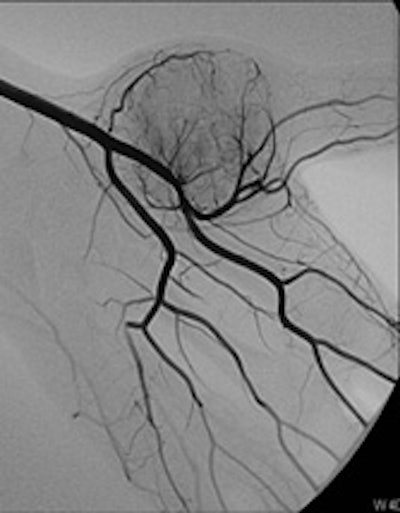

Bilbao's keen interest in interventional radiology began during the third year of his residency in 1982.

In the third year of my residency in 1982, I began to be attracted by the new way to perform interventions through percutaneous and endovascular approaches, and for a few months I went to the MD Anderson Center in Houston, Texas, U.S. There I took an important decision, which was that I would like to be completely involved in interventional radiology (IR), and with the great support of the CUN, this is what I have done for the rest of my professional life.